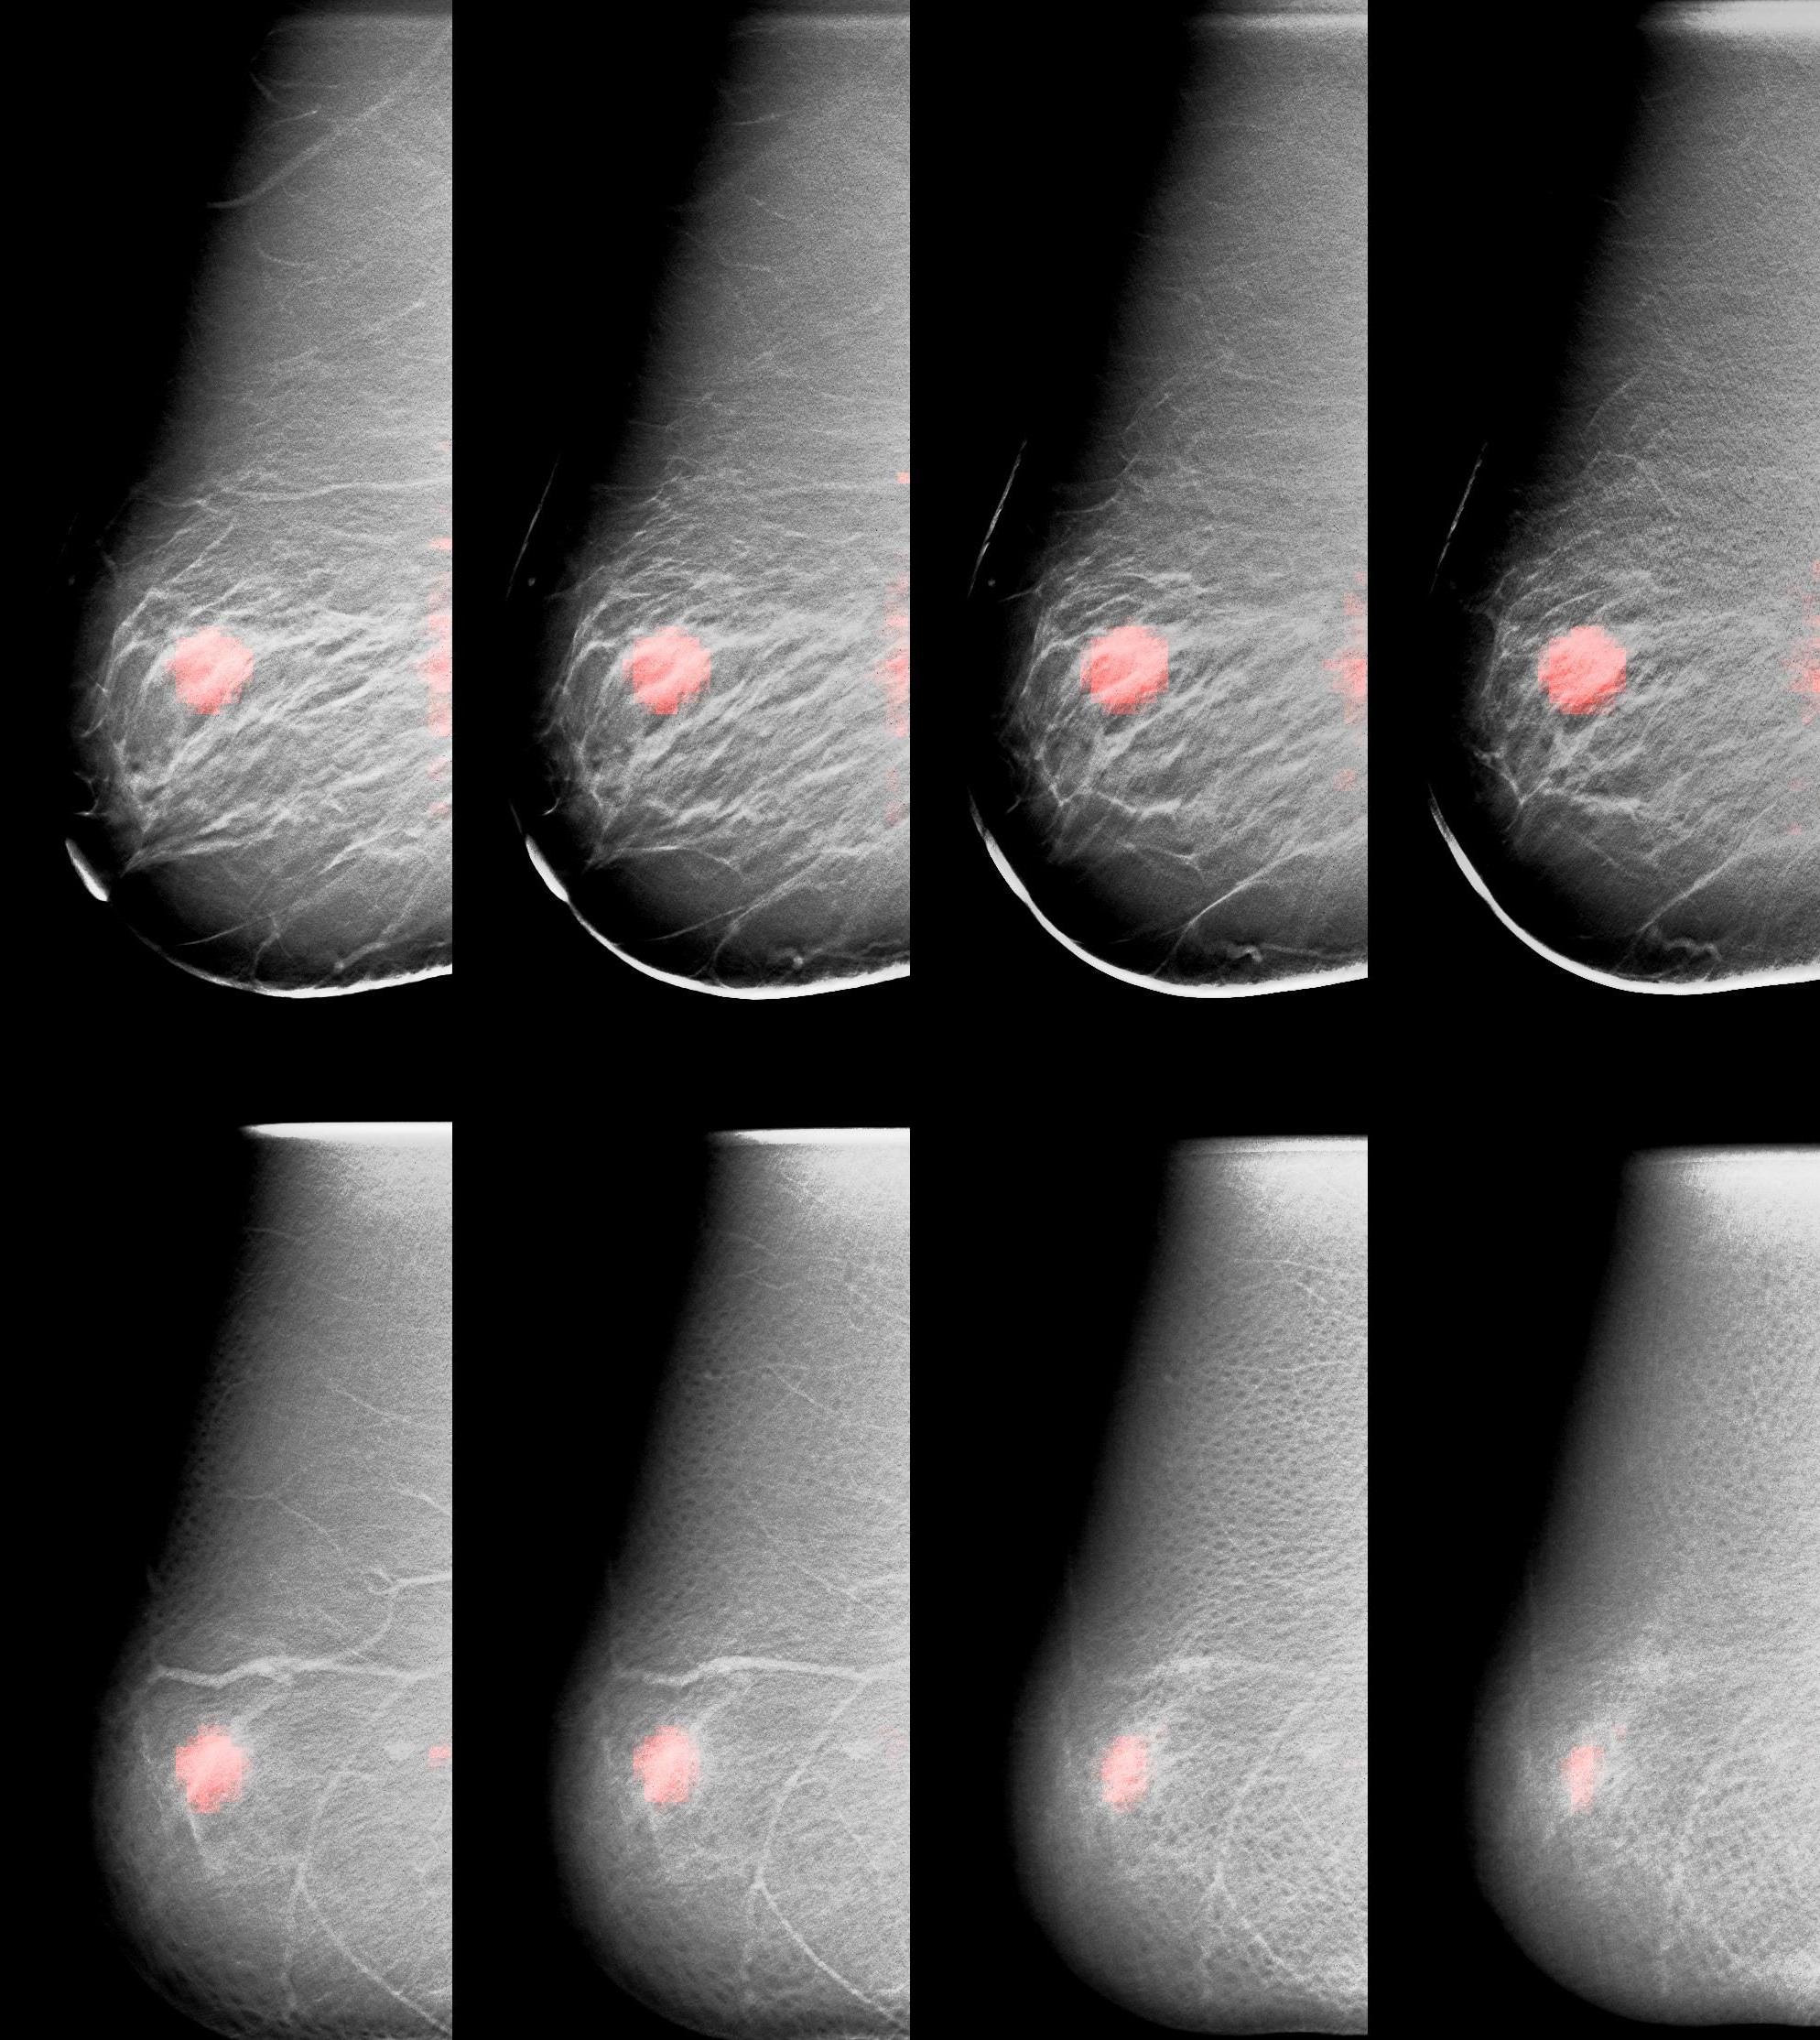

A montage showing the fusion of slices taken with X-ray and molecular breast tomosynthesis

Williams’ solution is to employ a technique called tomosynthesis to separate the superimposed elements and produce three-dimensional versions of both his X-ray and molecular scans. In dual modality tomosynthesis, the DMT scanner takes a series of X-ray images of the breast at slightly different viewing directions across an arc that ranges from 15 to 45 degrees. This is immediately followed by a series of images of the tracer over a range of viewing angles. The images of each modality are combined mathematically to construct a series of planes (slices) that a radiologist can examine individually.

This three-dimensional view is clearer: smaller and subtle abnormalities are more readily apparent because they are not embedded in background information. Having both the X-ray slices and their corresponding tracer slices available permits the radiologist to simultaneously assess both anatomical and physiological information about an abnormality and characterize it more accurately.